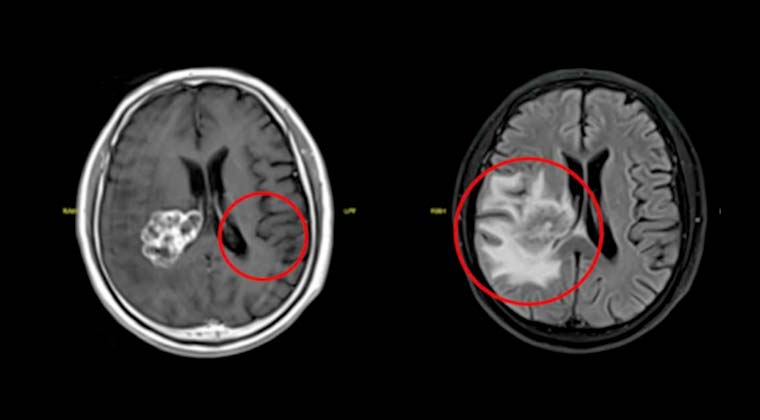

① Случай 1:

Пациентка, 38 лет

Комплексное лечение рака прямой кишки на протяжении почти 3 лет, головные боли в течение более 1 месяца.

Диагноз: Множественные метастазы в головной мозг при раке прямой кишки (стадия IVB, HER-2-положительный). Ранее проведённая химиотерапия и таргетная терапия оказались неэффективными, выявлены множественные внутримозговые метастатические очаги.

В апреле 2025 года в нашей клинике выполнена SBRT (стереотаксическая радиохирургия HyperArc) по поводу очагов в головном мозге, 40 Гр / 10 фракций.

Через 5 месяцев после лечения контрольное МРТ головного мозга показало практически полное исчезновение опухолевых очагов (G-PR). Качество жизни пациентки хорошее.

Изображение слева: до лечения

Изображение справа: после лечения